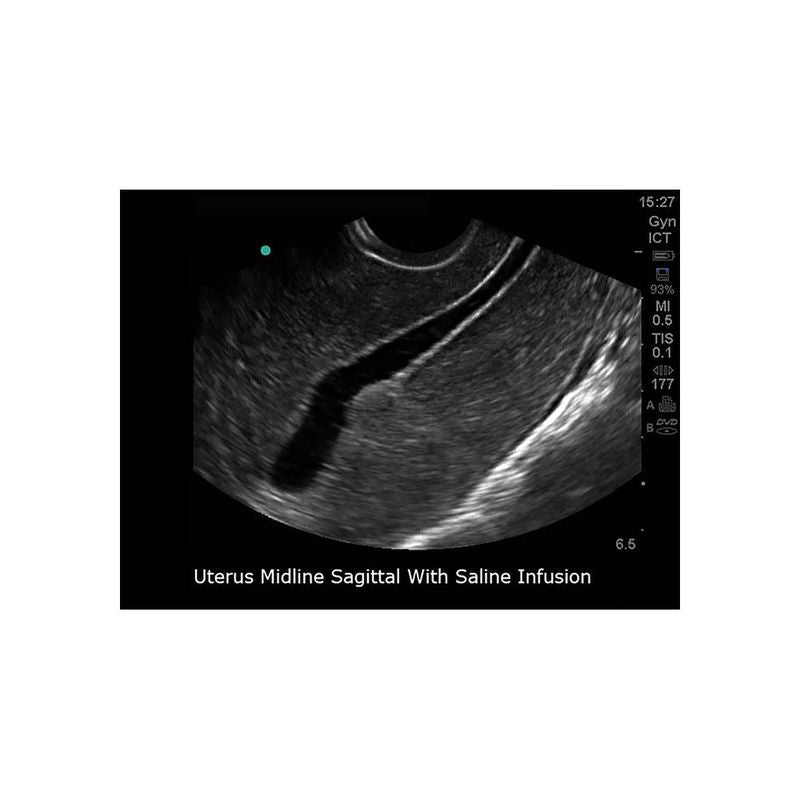

Gain proficiency in performing transvaginal ultrasound exams with our CAE Blue Phantom female pelvis models. The patented Simulex internal tissue allows learners to develop, practice and verify ultrasound imaging skills, including using ultrasound system controls, positioning and moving the transducer, recognizing internal pelvic anatomy and pathology and using gynecological ultrasound calculation packages to measure cysts, masses, and other structures. These models are excellent for 2D, 3D, and 4D ultrasonography imaging techniques. Choose from three options: General Pathology, Intrauterine & Ectopic Pregnancy, or Sonohysterographay & Sonosalpingography.

Sonohysterography & Sonosalpingography ANATOMY:

- Endovaginal canal

- Cervix

- Cervical canal

- Uterus

- Endometrial canal

- Fibroids

- Bladder

- Patent fallopian tubes

- Bowel